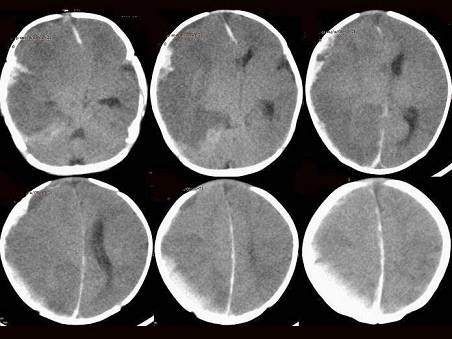

问题 女,2个月。患儿发烧、面黄、哭闹、精神差1周,双目直视。影像学检查如图,最可能的诊断为?(?)

选项 A.脑梗塞 B.脑水肿 C.VitK缺乏颅内出血 D.血管畸形 E.先天性大脑发育不良

答案 C